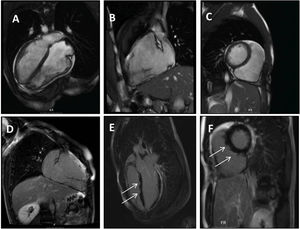

Clinical caseWe report the case of a 17-year-old federated soccer player who sought emergency care following an episode of palpitations and dizziness while playing soccer. He reported having already had two episodes of syncope upon exertion in the last six months but did not value them and therefore did not go to the emergency room. He denied any other personal history, regular consumption of drugs or narcotics and any relevant family history, including a history of SCD. The patient was tachycardic (218 bpm) and hypotensive (85/56 mmHg). A 12-lead ECG was performed which revealed wide complex tachycardia with left bundle branch block morphology and superior axis (Figure 1). Given the hemodynamic instability, the patient underwent electrical cardioversion with a biphasic shock of 50 joules and reverted to sinus rhythm. The ECG in sinus rhythm showed a T-wave inversion of V1–V5, with no other alterations (Figure 1). From laboratory tests, only a slight elevation of troponin I (0.97 ng/ml) was noteworthy. A transthoracic echocardiogram showed a non-dilated LV with good global systolic function, slight RV dilation and slight depression of its function (FAC) of 29%), with no other changes (Figure 2). The patient was hospitalized and underwent cardiac magnetic resonance imaging (CMR). CMR showed marked RV dilatation (end-diastolic volume indexed to body surface area of 180 ml/m2) by global hypokinesis with mild depression of its function (42%) and desynchrony. The late enhancement images showed subepicardial late enhancement in the distal septum and two small foci of subepicardial late enhancement in the middle segment of the inferoseptal wall (Figure 3). Thus, according to the 2010 TFC for the diagnosis of ARVC, the patient had three major criteria for the diagnosis of ARVC, including morphofunctional changes (areas of hypocontractility with a FAC ≤33%; desynchrony and RV end-diastolic volume indexed to body surface area ≥110 ml/m2), repolarization changes (inverted T-wave of V1–V5 in the absence of criteria for complete right bundle branch block), arrhythmia (sustained ventricular tachycardia with LBBB morphology and superior axis). Thus, taking into account that only two major criteria are needed for its diagnosis, the diagnosis of ARVC was made. Also, during hospitalization, the patient was implanted with a subcutaneous cardioverter-defibrillator (Figure 4). The patient remained asymptomatic throughout hospitalization. He was discharged with low-dose beta-blocker medication and contraindication for practicing sports. He is in regular follow-up in the Cardiology consultation, and adheres to the prescribed medication and recommendations, having, to date, no record of any new arrhythmic events. During follow-up, a genetic test was requested and enabled the identification of a pathogenic mutation categorized as associated to ARVC – variant c.1044_104dupAAAT (p.Asp350Lysfs*2) in the DSC2 gene which encodes the desmocholine-2 protein, and is implicated in the pathogenesis of ARVC. Thus, the patient has four major diagnostic criteria. A Holter was also requested which showed a number of ventricular extrasystoles >500 per day, fulfilling a minor criterion for the diagnosis. Currently, the patient does not participate in high-level sports nor any type of recreational sport.

Panel A–C: CINE CMR images showing marked RV dilatation (end diastolic volume indexed to body surface area of 180 ml/m2), global hypokinesis and dyssynchronous RV contractility with mild depression of its function (42%); Panel D–F: late-enhanced CMR showing subepicardial late enhancement in the distal septum and two small foci of subepicardial late enhancement in the middle segment of the inferoseptal wall (arrows).